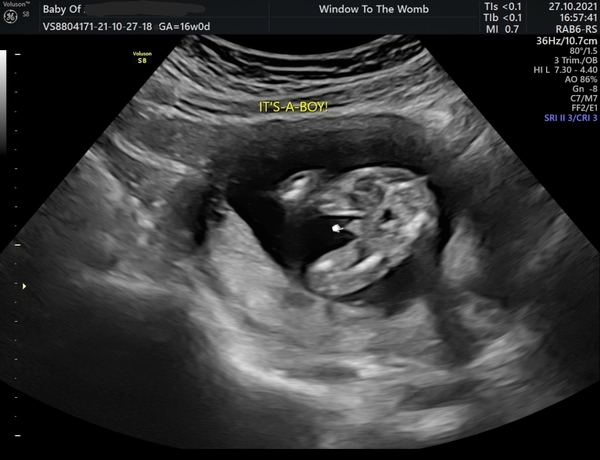

Its a boyyyy. 16+1 today! 😁💙